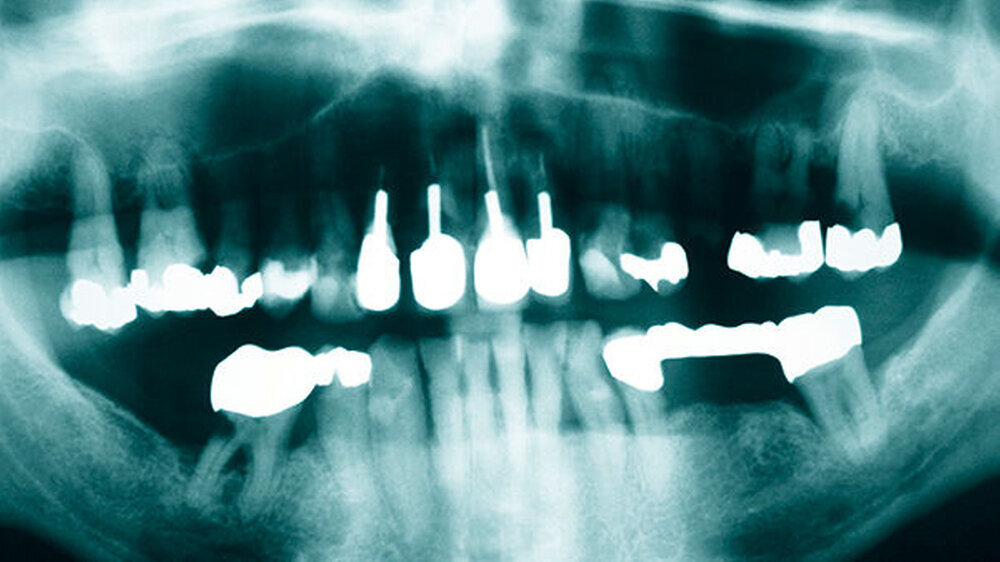

Die Abbildungen 4 bis 8 zeigen die Situation nach vier monatiger ZE-Tragezeit. Nach ausgiebiger Extraktionstherapie und parodontaler Behandlung der Restzähne wurde im Oberkiefer eine Cover-Denture-Totalprothese inseriert und im Unterkiefer eine parodontal abgestützte Teleskopprothese mit verblendeten Teleskopen 34,35,44,45.